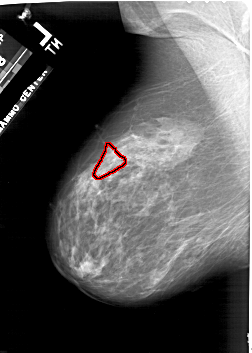

A_1941_1.RIGHT_MLO

RIGHT_CC LINES 5326 PIXELS_PER_LINE 3751 BITS_PER_PIXEL 12 RESOLUTION 43.5 NON_OVERLAY

RIGHT_MLO LINES 6271 PIXELS_PER_LINE 3811 BITS_PER_PIXEL 12 RESOLUTION 43.5 NON_OVERLAY